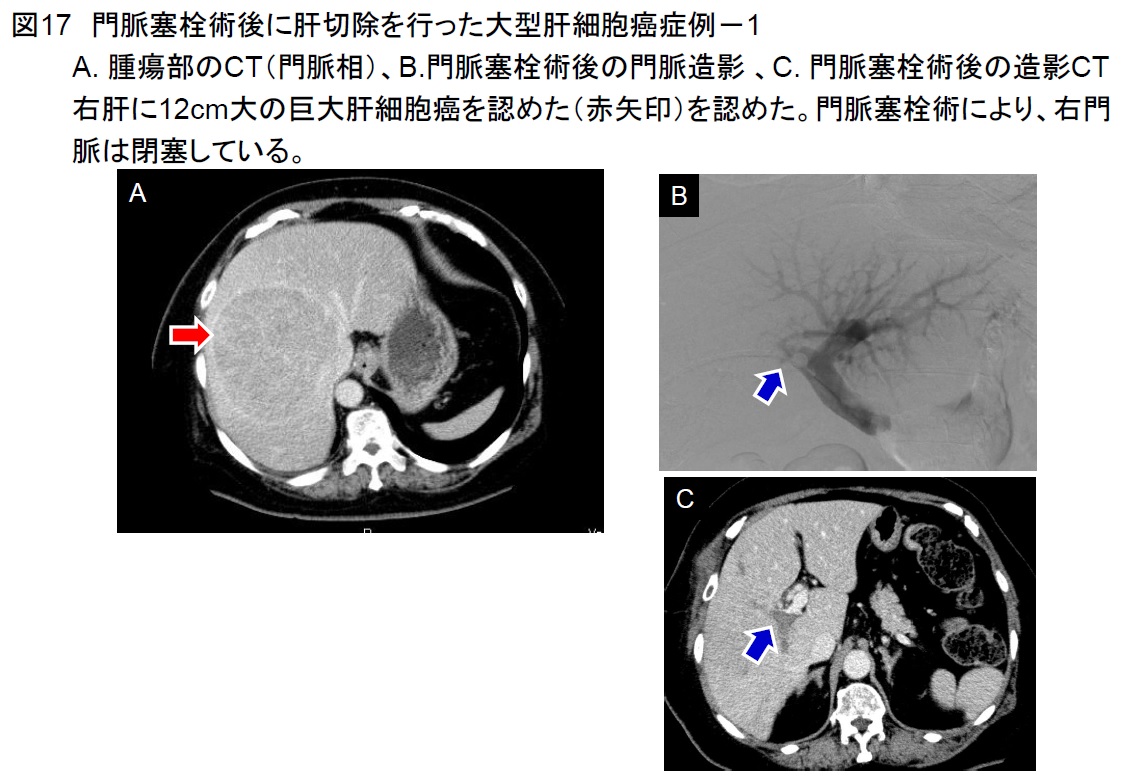

2017年に腹腔鏡肝切除の施設認定を取得し、高難度手術を含めた腹腔鏡肝切除を積極的に行っています(図12)。その他に肝切除例としては、緊急の肝動脈化学塞栓療法後に肝切除を行った症例(図13-16)や門脈塞栓術後に肝切除を行った大型肝細胞癌症例を経験しました(図17-19)。いずれも経過は極めて良好です。肝切除の適応決定時には、3次元画像解析シナプスVINCENTTMによる肝体積評価やアシアロSPECT-CT 融合画像による機能的肝体積評価を行い、より安全な手術を目指しています(図20)。